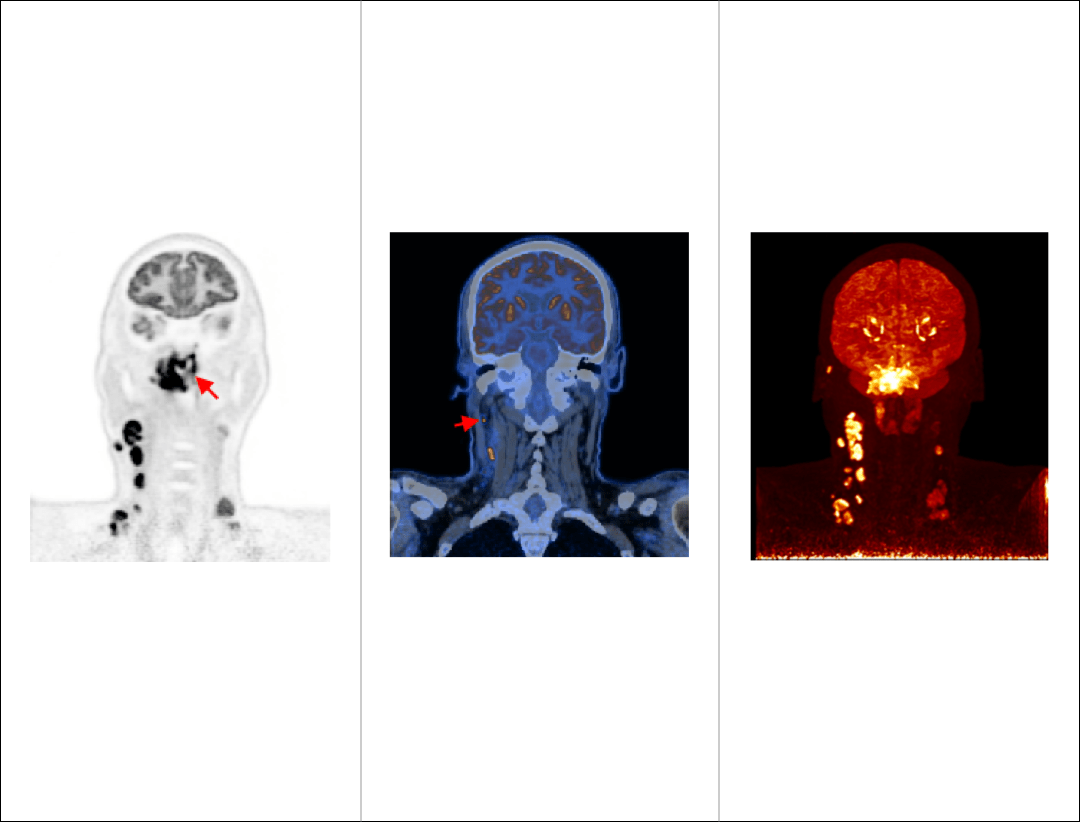

微小淋巴结高清显像

鼻咽癌头颈部单床位大范围扫描